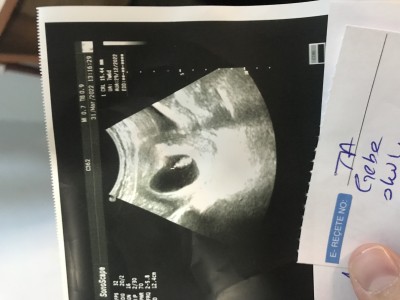

Çok şükür hiçbir sıkıntı yokmuş buda bebişim bugün tam 2 aylık olduk